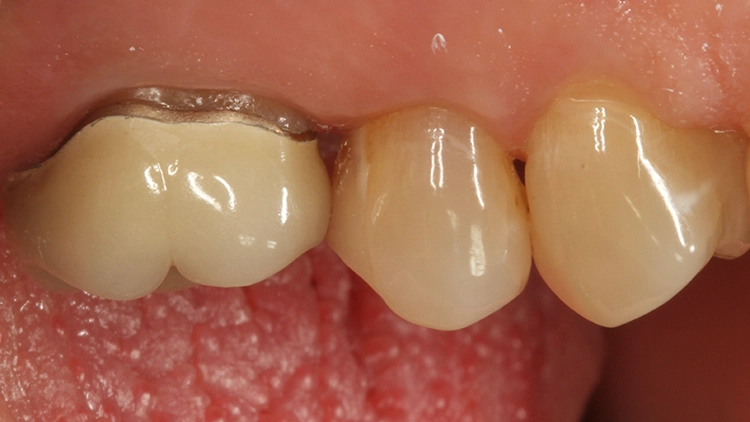

Die Abbildung 6 zeigt die fertig ausgearbeitete (H390Q und 48LQHartmetallfinierer, Komet, Lemgo) und polierte (Diacomp plus Twist DT-DCP10m und DT-DCP10f, EVE Ernst Vetter GmbH, Keltern) Restauration, die sich ästhetisch perfekt in die umgebende Zahnhartsubstanz einfügt. Die Approximalkontakte sind straff, die anatomische Form des Zahnes ist korrekt und die Patientin ist mit dem schnellen Versorgungsergebnis nach 45 Minuten sehr zufrieden.

Die weitere Versorgung der Kavität erfolgte analog zu Fall 1 nach Anwendung eines klassischen Etch&Rinse-Mehrflaschenadhäsivs und schichtweiser Applikation und Polymerisation von Venus Diamond ONE (Kulzer) mit einem Hochleistungs-LED-Polymerisationsgerät > 1.000 mW/cm2 für jeweils 20 Sekunden Lediglich anstelle des Venus Diamond Flow Baseliners kam aufgrund der sehr hohen ästhetischen Ansprüche des Patienten Venus Diamond Flow in der Farbe A2 zum Einsatz – der Patient hätte keinen weiß-opaken Rand an seiner Restauration akzeptiert. Das Ergebnis (Abb. 9) überzeugte den Patienten nicht nur funktionell, sondern vorrangig ästhetisch: Auch hier passt sich die Universalfarbe perfekt an die Zahnhartsubstanz an. Zur Überprüfung der Ausdehnung der Überkappung wurde im Anschluss an die Versorgung eine Zahnfilm-Röntgenaufnahme erstellt (Abb. 10).

Das Bild zeigt den perfekten Randschluss der Restauration in Kombination aus Venus Diamond Flow A2 und Venus Diamond ONE. Beeindruckend ist zudem die sehr hohe Röntgenopazität des Materials. Das pulpanahe, weniger röntgenopake Material ist das TheraCal LC-Überkappungsmaterial.